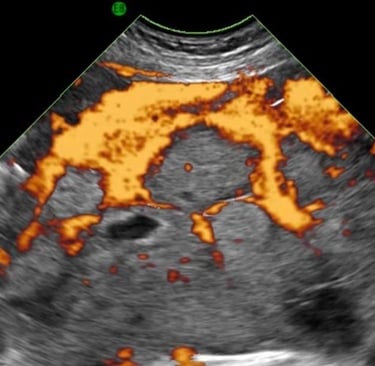

Advanced ultrasound diagnostics for precise tissue perfusion analysis that will enable a transformation in care

Validated quantification of tissue perfusion for better diagnostics

We characterize tissue perfusion to give reproducible metrics that allow us to better detect and characterise disease.